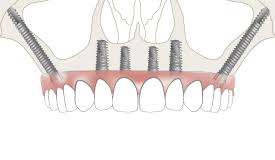

All-on-4/6 Implants

Full-arch teeth replacement using four strategically placed implants.

Zygomatic Implants

Alternative implants anchored in the cheekbone for severe bone loss.